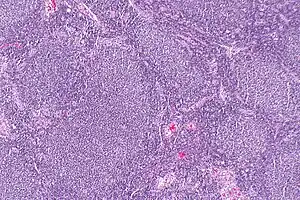

Linfoma folicular

Linfoma folicular, linfoma centrolástico, linfoma nodular ou doença de Brill-Symmers[1] é um tipo de câncer que se origina nos linfócitos B nos folículos dos linfonodos e representa cerca de 20 a 30% dos Linfoma não Hodgkin.